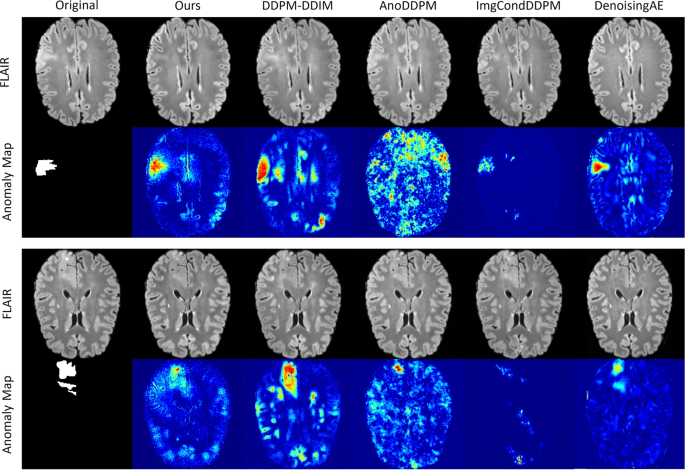

Visualization of typical anomaly detection results on UHB dataset. The red color in the Anomaly Map means that the reconstructed image differs significantly from the original image, while the blue color means that there is basically no difference.

The study compares various models on the UHB dataset, including diffusion-based and autoencoder-based methods such as AnoDDPM 9, ImgCondDDPM 10, DDPM-DDIM 11, and DenoisingAE 20. To ensure fair comparison, we used default parameters from the open-source code of each competing method, matching the data to the training period. Our method demonstrated superior performance, achieving higher recall rates and fewer false positives than alternative approaches, as summarized in Table 1. Furthermore, Fig. 3 illustrates that our method closely approximates the true detection of epileptic foci.

In four experiments, our method achieved recall scores of 0.856 and 0.952, and Dice scores of 0.245, for R@5 and R@10 respectively, both representing the highest scores. On average, recall exceeded other methods by 0.318 and 0.173, while Dice scores were higher by 0.099. These results indicate that AnoDDPM, employing an unsupervised algorithm, struggles to identify epileptic features, with error accumulation due to Markov chain denoising. Conversely, the unsupervised algorithm ImgCondDDPM, with conditional bootstrapping, significantly reduces false positives but still encounters broken loop anomalies instead of transformed anomalies. Compared to the DDPM-DDIM method, which uses a weakly supervised strategy, our approach integrates positional and modal information for enhanced detection accuracy. Additionally, compared to DenoisingAE, which relies on a classical self-supervised denoising architecture with UNet at its core, our method employs a more generative diffusion model architecture, resulting in improved anomaly transformation.